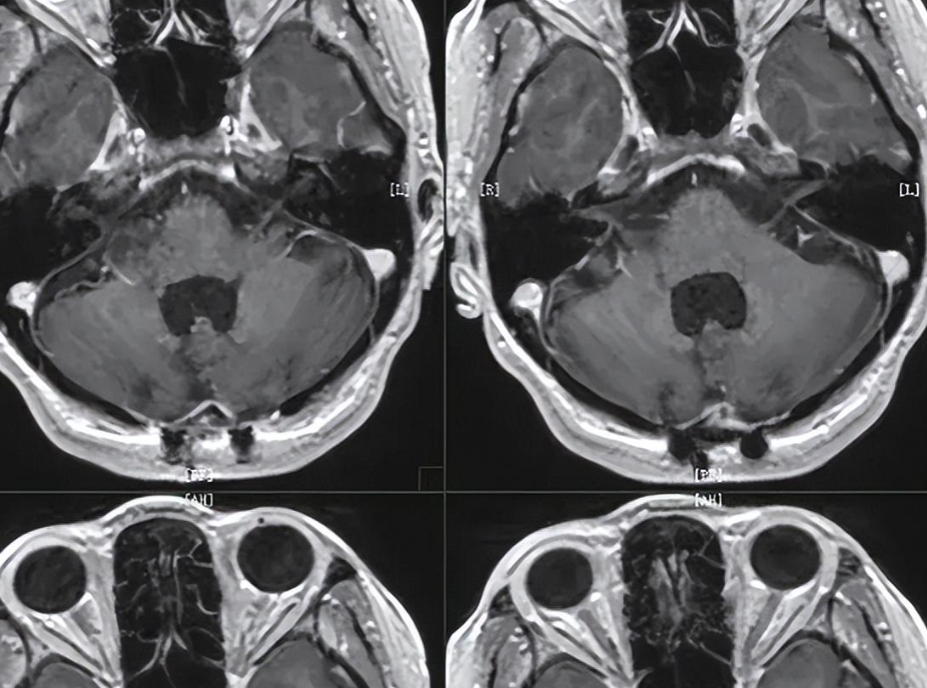

它可是检查神经系统的得力助手哦,比如大脑里的问题,像急性脑梗塞、脑出血,还有脑肿瘤,都逃不过它的“法眼”。

磁共振能准确找出脑内肿瘤的位置,还能确定肿瘤的大小,给医生治疗提供重要的参考。